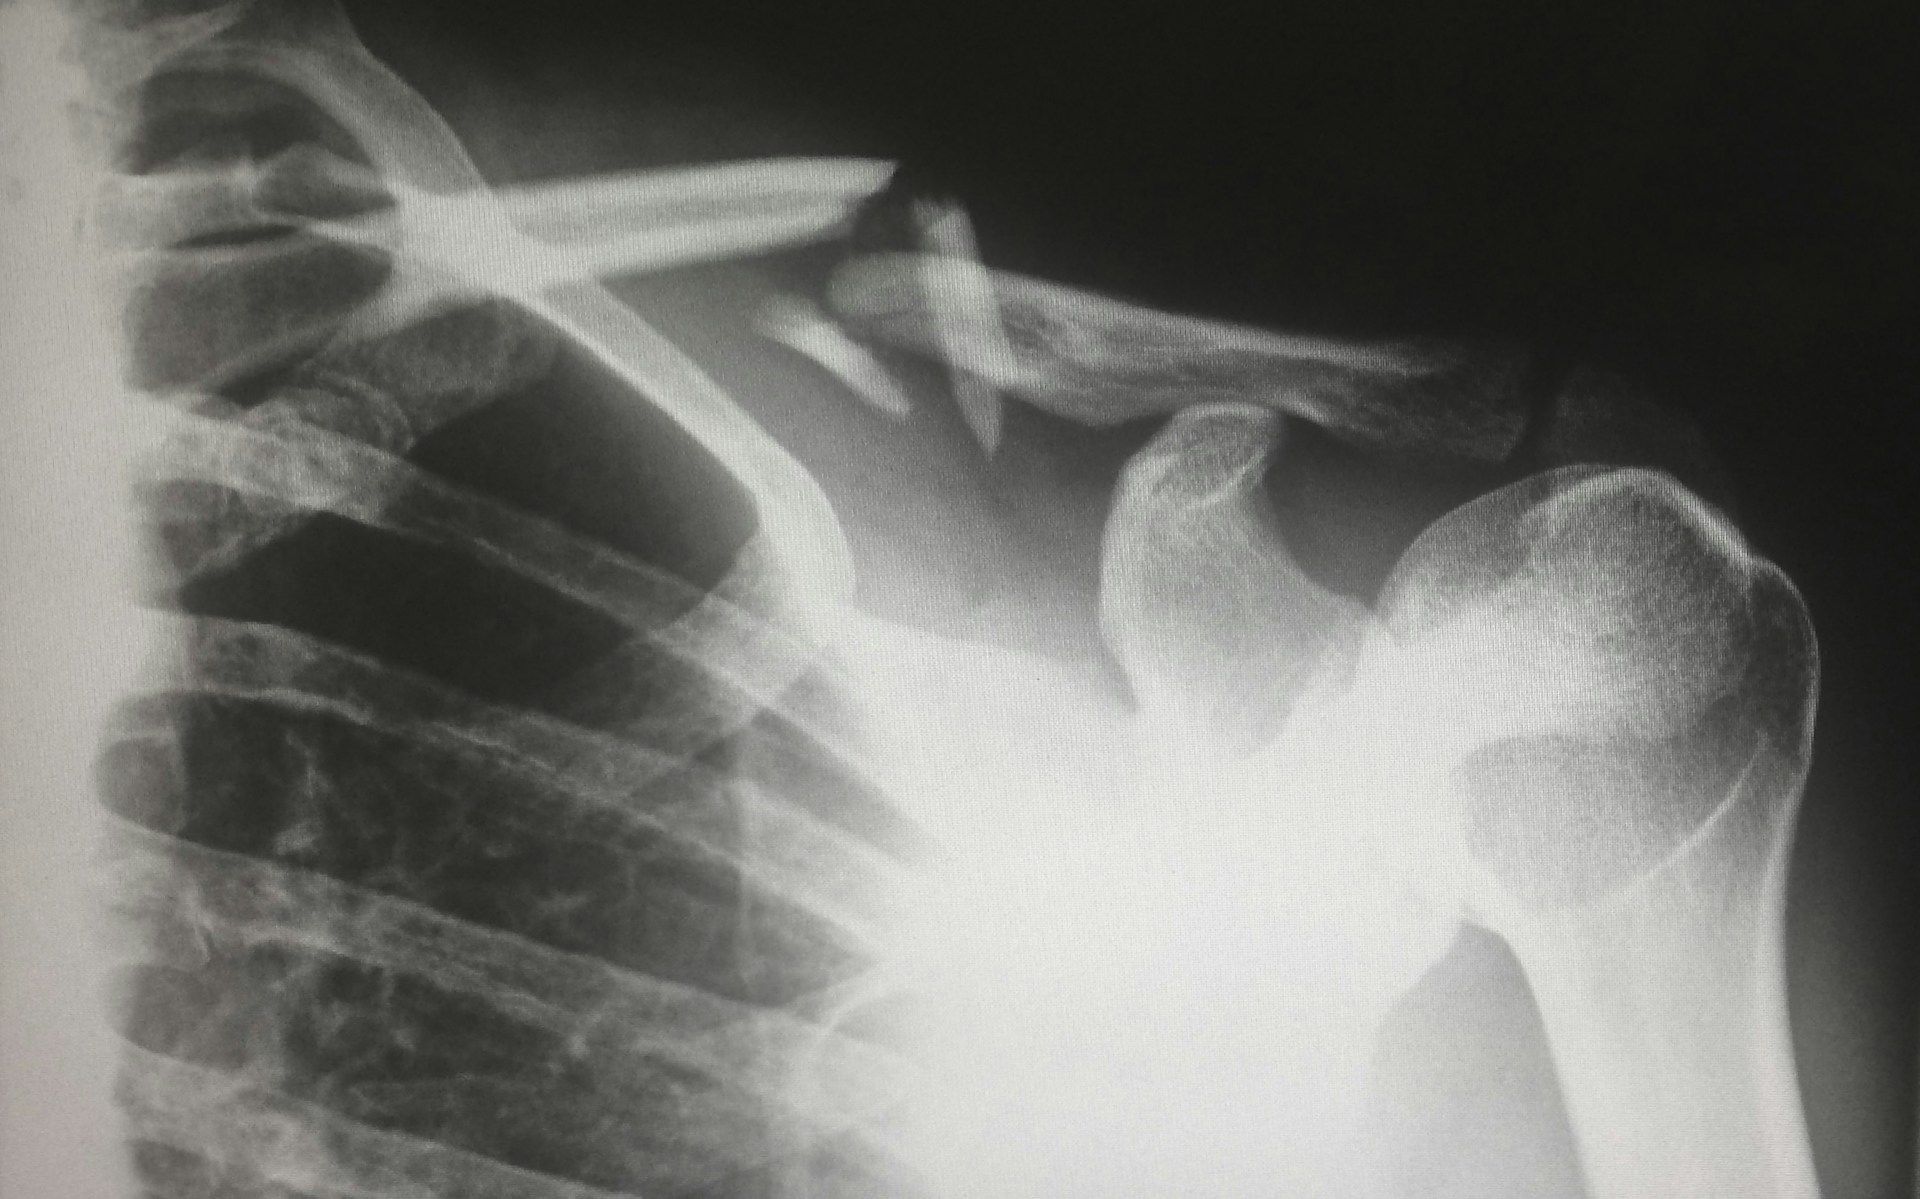

Эта инновация уже прошла испытания на 150 пациентах: во многих случаях то, что раньше требовало металлоконструкций и сложных операций, теперь решается за три минуты с помощью нового клея.

Клей Bone-02 особенно перспективен для экстренной медицины и лечения тяжелых обломочных переломов, когда на счету каждая минута, а надежность фиксации критически важна.